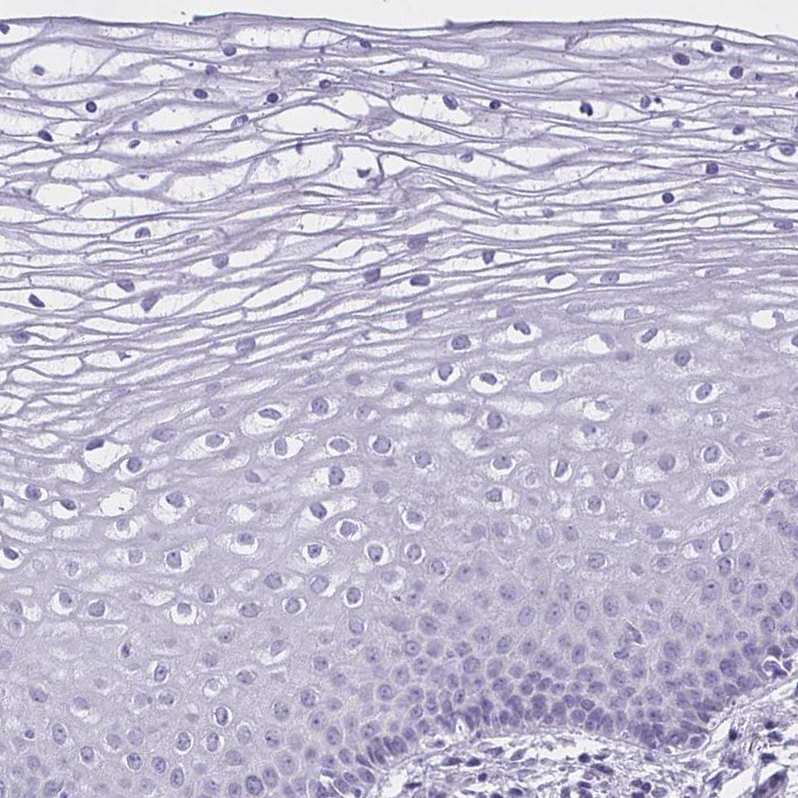

Immunohistochemical staining of human testis shows weak granular cytoplasmic positivity in cells in seminiferous ducts.